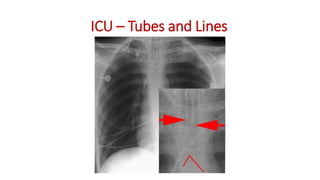

ICU – Tubes and Lines

Ryles Tube

Central

Venous

Catheter

Artificial

Valves

ICU – Tubesand Lines